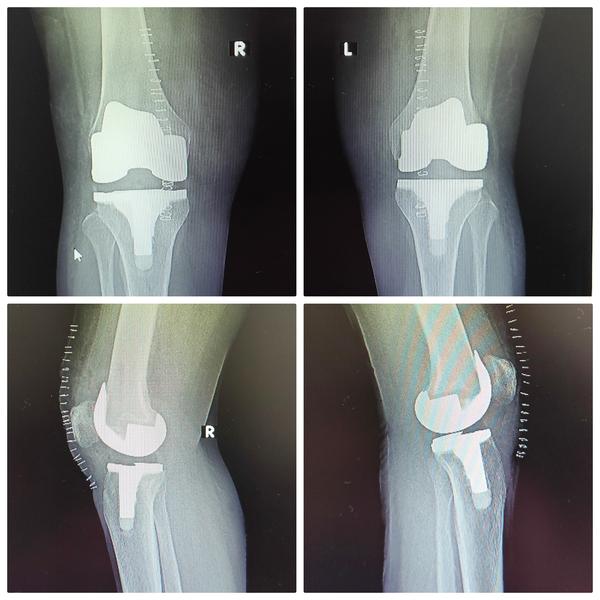

Robotic Knee Replacement Surgery is an advanced surgical technique that utilizes robotic assistance during knee replacement surgery to improve precision and outcomes. Here's how it works:Preoperative Planning: Before the surgery, the surgeon uses advanced imaging techniques, such as CT scans or MRI, to create a 3D model of the patient's knee. This detailed preoperative planning allows for a customized surgical approach.Navigation Assistance: During the surgery, the surgeon uses a robotic system that includes a computer and a robotic arm. The 3D model of the patient's knee is loaded into the computer, providing a real-time, high-resolution view of the knee joint.Surgical Precision: The robotic arm is controlled by the surgeon but offers enhanced precision and control. It assists the surgeon in making precise cuts in the bone and accurately positioning the implant components.Feedback and Safety Measures: The robotic system provides real-time feedback to the surgeon, ensuring that the planned cuts and implant placements are executed accurately. It can also prevent the surgeon from making any movements that could potentially damage surrounding tissues.Customized Approach: Robotic knee replacement allows for a highly customized approach, taking into account the patient's unique anatomy and the extent of joint damage. This can lead to a better fit and alignment of the artificial knee components.Less Invasive: Robotic-assisted surgery often requires smaller incisions than traditional knee replacement surgery. This can lead to less tissue damage, reduced pain, and a quicker recovery.Faster Recovery: Patients who undergo robotic knee replacement surgery may experience a faster recovery and shorter hospital stays compared to traditional surgery.Improved Long-Term Outcomes: The precise alignment and positioning of the knee implant components can contribute to improved long-term outcomes, including better joint function and longevity of the implant.